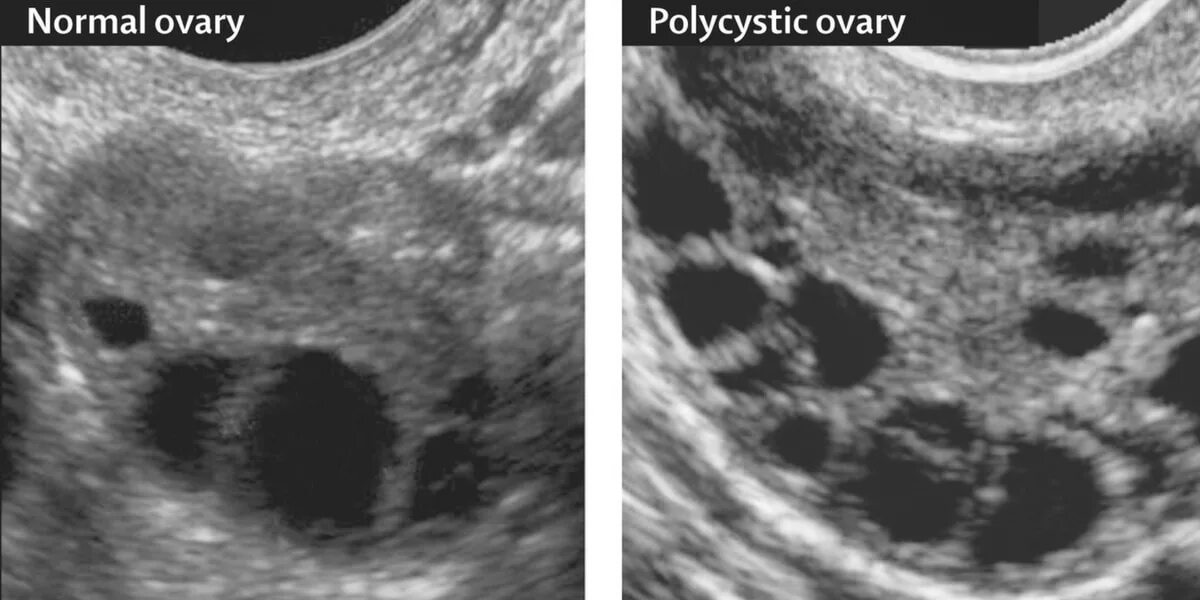

Как выглядит поликистоз яичников